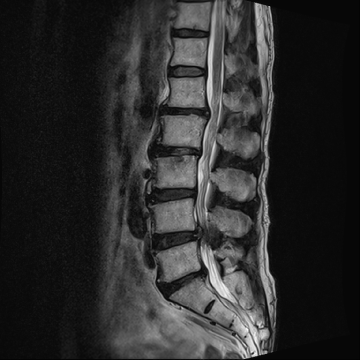

요추 협착증 수술 전·후

2020.08.30

2022.09.06

ㆍ환자 동의를 받은 자료이며, 이미지 사진은 실물과 다를 수 있습니다.

ㆍ모든 자료는 새움병원 자료입니다.